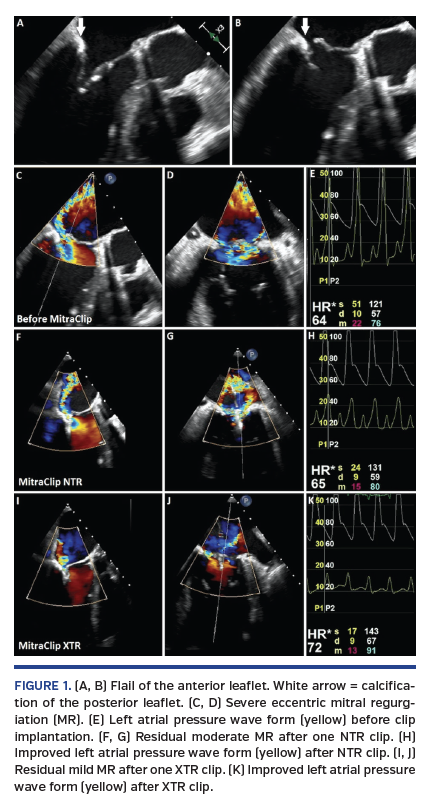

An 89-year-old man presented with dyspnea (New York Heart Association class IV). He had undergone coronary artery bypass graft and surgical aortic valve replacement. Transesophageal echocardiography (TEE) revealed severe mitral regurgitation (MR) with flail anterior leaflet, calcified posterior leaflet (Figures 1A-1D; Videos 1 and 2) and high left atrium pressure (LAP) (Figure 1E). Transcatheter edge-to-edge repair using the MitraClip (Abbott Vascular) was performed. Considering the calcified posterior leaflet, we chose NTR to avoid the leaflet damage. However, there was still moderate MR after we grasped the A2/P2 segments using one NTR clip (Figures 1F and 1G) with significant LAP improvement (Figure 1H; Video 3). We decided to retrieve the NTR and implanted an XTR clip in the same position. We then achieved better MR reduction without any leaflet damage (Figure 1I and 1J; Video 4) and further reduction of LAP (Figure 1K).

The MitraClip XTR has longer clip arms than the NTR; thus, it effectively grasps more leaflet tissue. The XTR clip has a potential risk of leaflet damage when grasping calcified leaflets; therefore, the XTR is considered unsuitable in this situation. As we demonstrated, the XTR clip can achieve a better outcome than the NTR clip even in the case of calcified leaflet. Now, we have the MitraClip G4, which offers an expanded range of clip sizes. Even in the current era of transcatheter edge-to-edge repair, deciding clip size in each case is still a challenge.